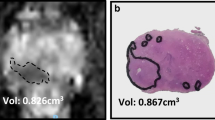

The DSC was 0.76 and 0.79, respectively, for pelvic lesions, and 0.37, 0.43, and 0.53 respectively for omental lesions (Fig. 3). We were not able to calculate a DSC for patient 1 as the tumour edges were not visible on the B-mode ultrasound images.

The accuracy of the CT/US fusion was associated with the tumour volume and was higher for pelvic compared to omental tumours. The dice similarity coefficient (DSC) was used to assess the accuracy of the CT/US fusion. The DSC was higher for the pelvic (larger) compared to that for the omental (smaller) tumours that yielded a low DSC. Dashed line, CT segmentation; solid line, US segmentation